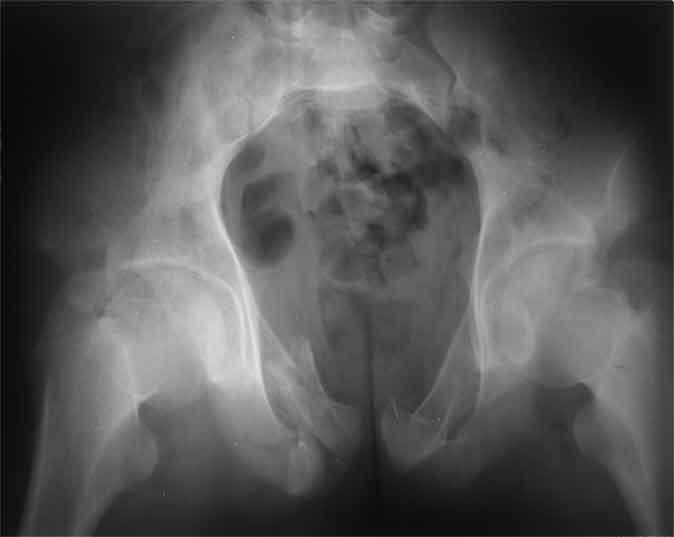

Не смог разглядеть на представленных картинках частичное повреждение левого КП, повреждение Денис1-2 справа? 3Д реконструкции в инлет и боковой проекциях убедительно не демонстрируют типа повреждения задних отделов тазового кольца(справа боковая масса скомпремирована), Наверное, у тебя есть возможность оценить тип перелома крестца по прямой проекции 3Д.

Думаю, что КТ заднего отдела показала бы ясно тип повреждения .

По вертлуге- смог разглядеть только изолированный перелом передней колонны.

Насколько я понял из твоего письма, обращенного к анонимному vit, ты не видишь показаний к реконструкции перелома. Я бы взялся за реконструкцию(илео-ингвинальный доступ), хоть прошел и месяц после травмы: боковая 3Д показывает смещение нагрузочной зоны впадины, что однозначно будет способствовать разрушению хряща головки и впадины( особенно у 16 летнего пациента с ожидаемым высоким уровнем активности) + изменение геометрии впадины за счет неустраненного смещения фрагментов колонны (КТ, 3Д данные).

На мой взгляд, без реконструкции этот сустав обречен (концепция вторичной конгруэтности в данных условиях работать не будет), реконструкция дает шанс на восстановление функции сустава.

В данном случае 3D и корональные срезы КТ менее информативны, чем поперечные. Согласен с левосторенним минимальным повреждением КПС, но не смог уловить перелом крестца.

На 3D по линии перелома ацетабулум возможно сверху в подздошной кости уже есть сращение? или состояние перелома у молодых, после неполного (при пластической деформации) перелома.

По представленным материалам, мне кажется, перелом был передней колонны ацетабулум с минимальным вовлечением нагрузочной поверхности сустава, левосторенний повреждение КПС и лонных костей.